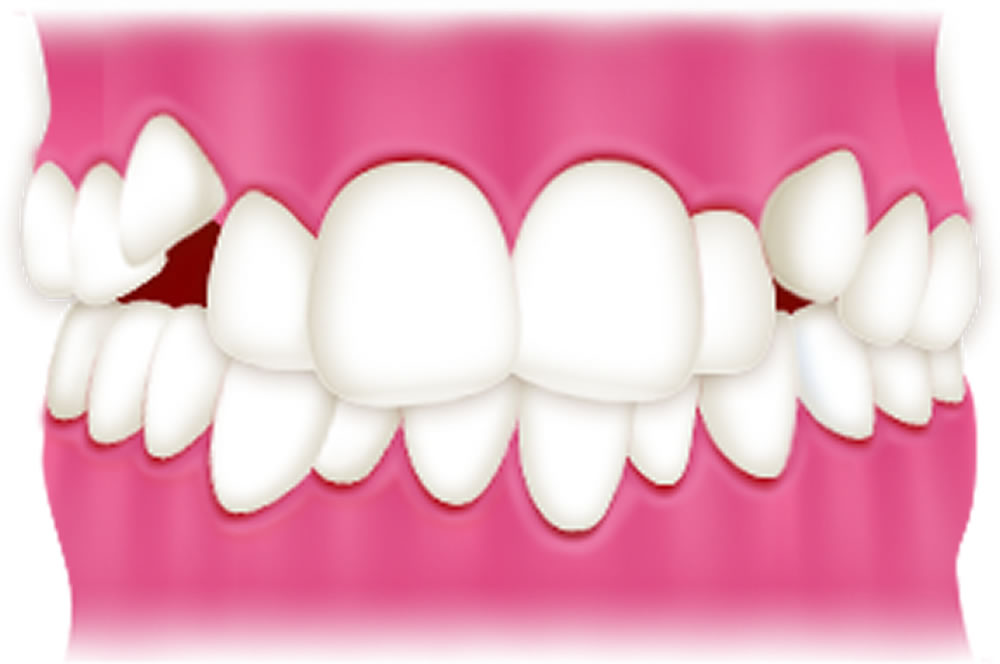

叢生

叢生とは、歯が重なってデコボコに並ぶ状態(乱ぐい歯)を指します。歯磨きがしにくく、虫歯や歯周病のリスクが高くなります。